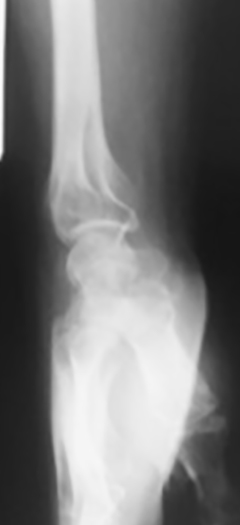

Paciente de sexo masculino, de 26 años, diestro, sin antecedentes personales a destacar, que fue embestido por automóvil mientras manejaba su moto. El paciente presentó una lesión encefálica focal que requirió tratamiento médico. Estuvo en coma 20 días, aparentemente sin otras lesiones. Luego, ya con vida de relación retomada, el paciente relató dolor e impotencia funcional de su mano derecha. Tumefacción y dolor a la movilización (pasiva-activa) y a la prehensión en el examen físico. Las radiografías y el TC mostraron una luxación volar de hueso grande de mano derecha (Figura 1) asociada a fracturas de la base del tercer metacarpiano y de hueso piramidal, ambas sin desplazamiento (Figura 2). A las 8 horas de establecer el diagnóstico se realizó una reducción abierta por vía palmar con fijación interna, con alambres de Kirchner de 1,5 mm, (Figura 3). Se agregó un mini fijador externo para proteger la estabilidad de la osteosíntesis del carpo y manejar las partes blandas lesionadas. No se realizó reconstrucción ligamentaria.